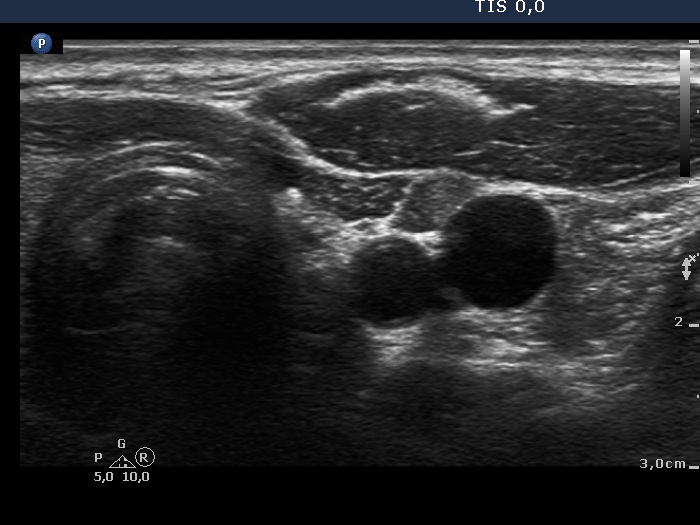

Ultrasonography revealed that the discrete hypoechoic lesion in the left lobe had increased in size, the dimensions were 4x4x5 mm, width, depth and length, respectively. There was a lymph node lateral to the left lobe. The node presented a heterogeneous pattern and lacked a regular hilum.Suggestion: repeat ultrasound in 3 to 6 months.

The small hypoechoic lesion within the left thyroid corresponds to a remnant. It seems to be realistic that this is thyroid tissue, but we have no particular reason to assume it would be a malignant lesion.

-

However, the lymph node is suspicious, especially due to its heterogeneity.